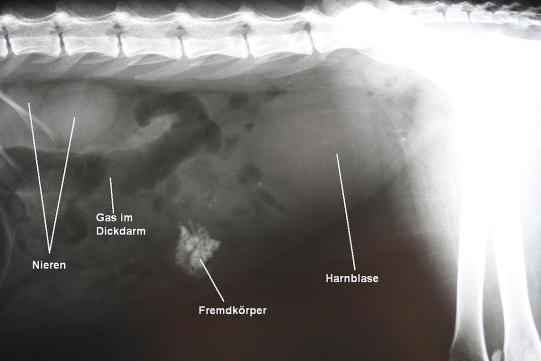

1 Woche später wird "Lucifer" ein weiteres Mal vorgestellt. Nachdem es dem Kater initial besser ging und er wieder einen guten Appetit zeigte, hat er in der Zwischenzeit wieder mehrmals erbrochen und zeigte wieder Appetitverlust. Bei der Untersuchung erscheint der Dickdarm nun leer, dafür ist ein Knoten von etwa 2 cm Durchmesser im Bauch tastbar. Ein weiteres Röntgen zeigt eine stark röntgendichte, sternförmig anmutende Struktur, welche schon bei der vorherigen Röntgenaufnahme sichtbar gewesen war, damals aber ebenfalls als Kot im Dickdarm interpretiert worden war. Ein kurzer Ultraschalluntersuch bestätigt den nun dringenden Verdacht eines Darmfremdkörpers, welcher den Darm verlegt.

Der Darmfremdkörper muss chirurgisch angegangen werden. Eine intravenöse Infusion wird verabreicht, um den Kreislauf zu stützen, und es werden ein Schmerzmittel und zwei Antibiotika verabreicht. In Narkose wird die Bauchhöhle eröffnet und das fragliche Dünndarmstück vorgelagert: Der Fremdkörper ist im oberen Drittel des Dünndarms gut durch die Darmwand tastbar. Durch das Durchquetschen des Gegendstandes ist die magenwärts gelegene Darmwand gerötet und gedehnt; an einer Stelle ist aufgrund der Entzündung der Darmwand das grosse Netz (eine schleierartige feine Struktur im Bauchraum) mit dem Dünndarm verklebt. Die Verklebung wird gelöst, die Darmwand im Bereich des Fremdkörpers aufgeschnitten und der harte, stachelige Gegenstand entfernt. Die anfängliche Idee, es könnte sich um ein Stück Igelhaut samt Stacheln handeln, wird aufgrund des Umstandes, dass "Lucifer" sich nur in der Wohnung aufhält, wieder verworfen. Die Besitzer erkennen in dem Gegenstand schlussendlich ein Stück eines Gummispielzeugs, welches die Katze vor längerer Zeit zerkaut und offensichtlich teilweise verschluckt hat. Durch den längeren Aufenthalt in der Magensäure ist der Gummi steinhart und röntgendicht geworden. Erst jetzt, nachdem sich der Gegenstand ungünstigerweise in den Dünndarm bewegt hat, haben sich aber Symptome entwickelt.